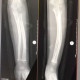

Alo dokter. Sy punya anak usia 3,6thn terjatuh saat bermain,hasil xray deformitas bowing os radius ulna Sinistra. Post pemasangan gips slma 3 mggu oleh Sp.B. Hasil foto xray kontrol msh sm dgn awal. Smntra di srh observasi dl,apa perlu di lakukan reduksi tertutup agar bs mngembalikan posisi tulangx?

Trma ksh sblmx alo dokter